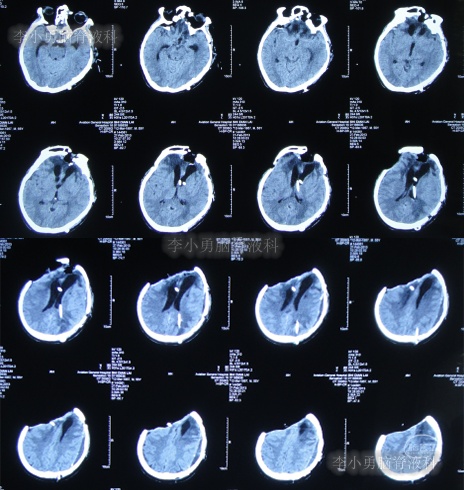

继续治疗1个半月,期间4次(2013年2月15日、2013年2月27日、2013年3月5日、2013年3月11日)查头颅CT(图-19、图-20、图-21、图-22)均示脑室在不断的变好。

图-19:2013年2月15日头颅CT

图-20:2013年2月27日头颅CT

图-21:2013年3月5日头颅CT

图-22:2013年3月11日头颅CT

2013年3月12日(入院治疗132天),拔除了头部外引流管(图-23)。

图-23:2013年3月12日头颅CT

2013年3月15日(入院治疗135天),查头颅CT示脑室周水肿减轻(图-24)。

图-24:2013年3月15日头颅CT